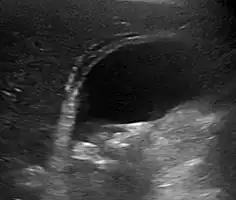

Right upper quadrant abdominal ultrasound is most commonly used to diagnose cholecystitis.[1][25][26] Ultrasound findings suggestive of acute cholecystitis include gallstones, pericholecystic fluid (fluid surrounding the gallbladder), gallbladder wall thickening (wall thickness over 3 mm),[27] dilation of the bile duct, and sonographic Murphy's sign.[13] Given its higher sensitivity, hepatic iminodiacetic acid (HIDA) scan can be used if ultrasound is not diagnostic.[13][14] CT scan may also be used if complications such as perforation or gangrene are suspected.[14]

Acute cholecystitis as seen on ultrasound. The closed arrow points to gallbladder wall thickening. Open arrow points to stones in the GB -